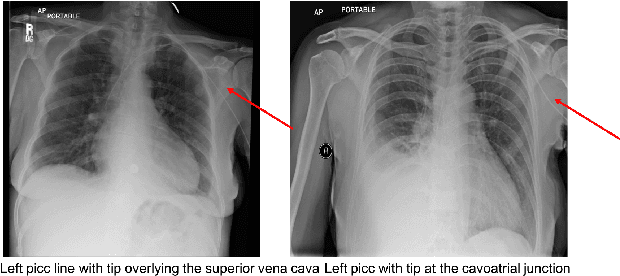

Abstract:Chest X-rays are the most common diagnostic exams in emergency rooms and hospitals. There has been a surge of work on automatic interpretation of chest X-rays using deep learning approaches after the availability of large open source chest X-ray dataset from NIH. However, the labels are not sufficiently rich and descriptive for training classification tools. Further, it does not adequately address the findings seen in Chest X-rays taken in anterior-posterior (AP) view which also depict the placement of devices such as central vascular lines and tubes. In this paper, we present a new chest X-ray benchmark database of 73 rich sentence-level descriptors of findings seen in AP chest X-rays. We describe our method of obtaining these findings through a semi-automated ground truth generation process from crowdsourcing of clinician annotations. We also present results of building classifiers for these findings that show that such higher granularity labels can also be learned through the framework of deep learning classifiers.